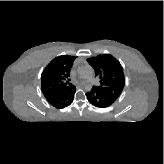

This section compares the reconstruction quality and runtime among the proposed MBIR method, PWLS-ST-, and other three MBIR methods, PWLS-EP, PWLS-DL, and PWLS-ST-. Table I shows that, for both 2D and 3D sparse-view CT reconstructions of the XCAT phantom, the proposed PWLS-ST- model outperforms PWLS-EP and PWLS-ST- in terms of RMSE. In addition, PWLS-ST- using a square transform (of size ) achieves lower RMSE than PWLS-DL using an overcomplete dictionary (of size ) for 2D sparse-view reconstructions. Fig. 3(a) and Fig. 4 show the reconstructed images for 2D and 3D phantom experiments, with different reconstruction models and different number of views. (See the corresponding error maps in the supplement.) The proposed PWLS-ST- consistently gives more accurate image reconstructions compared to other MBIR methods. Specifically, PWLS-ST- has smaller errors in the heart region (see zoom-ins in Fig. 3(a)) of 2D reconstructions than PWLS-DL and PWLS-ST-. In addition, compared to PWLS-ST-, PWLS-DL and PWLS-ST- have some ringing artifacts around the edges with high transition, e.g., edges between air and soft tissues. (See a comparison of profiles of PWLS-ST- and PWLS-ST- in the supplement.) In particular, PWLS-ST- and PWLS-DL give more visible ringing artifacts for 2D reconstruction from fewer views, and PWLS-ST- has these ringing artifacts for 3D reconstructions regardless of the number of views (see zoom-ins in Fig. 4). Table II reports runtimes of different MBIR methods in reconstructing the -views XCAT phantom scan. (FBPConvNet is a non-MBIR method and its runtime for processing a image is approximately one second with a TITAN Xp GPU.) While providing better reconstruction quality, the proposed Algorithm 1 of PWLS-ST- has shorter runtime compared to the algorithms of PWLS-DL and PWLS-ST- in Section III-A. Similar to the PWLS-EP algorithm, the reconstruction time of the PWLS-DL, PWLS-ST-, and PWLS-ST- algorithms can be further reduced by using ordered subsets [51].

Fig. 3(b) shows that when tested on the clinical scan data, the proposed PWLS-ST- method improves reconstruction quality in terms of noise and artifacts removal (e.g., see zoom-ins for soft-issue regions), and edge preservation (e.g., see zoom-ins for bone regions), compared to PWLS-EP and PWLS-ST-. Compared to PWLS-DL, PWLS-ST- achieves comparable image quality, but requires less computational complexity.

The benefit of the proposed PWLS-ST- over PWLS-ST- can be explained when there exist some outliers for some : in (12) gives equal emphasis to all sparse codes – from small to large coefficients that generally correspond to edges in low- and high-contrast regions, respectively – in estimating ; however, PWLS-ST- adjusts to mainly minimize the outliers, i.e., it may not pay enough attention to reconstruct regions with small coefficients. The histogram results in Fig. 1 reveal model mismatch of PWLS-ST- over the iterations. Fig. 3, Fig. 4, and Table I show that PWLS-ST- can moderate model mismatch, and provides more accurate reconstruction than PWLS-ST-.